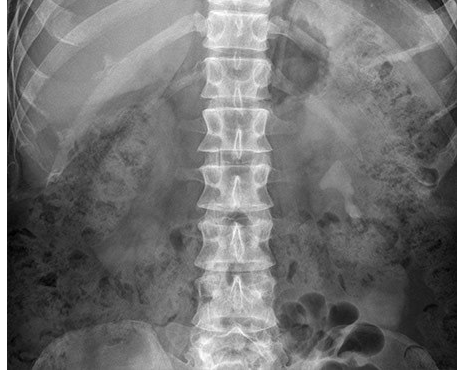

What is the cause of the abnormal calcification?

Adrenal calcification

Appendicolith

Gallstones

Pancreatic calcification

Staghorn renal calculus